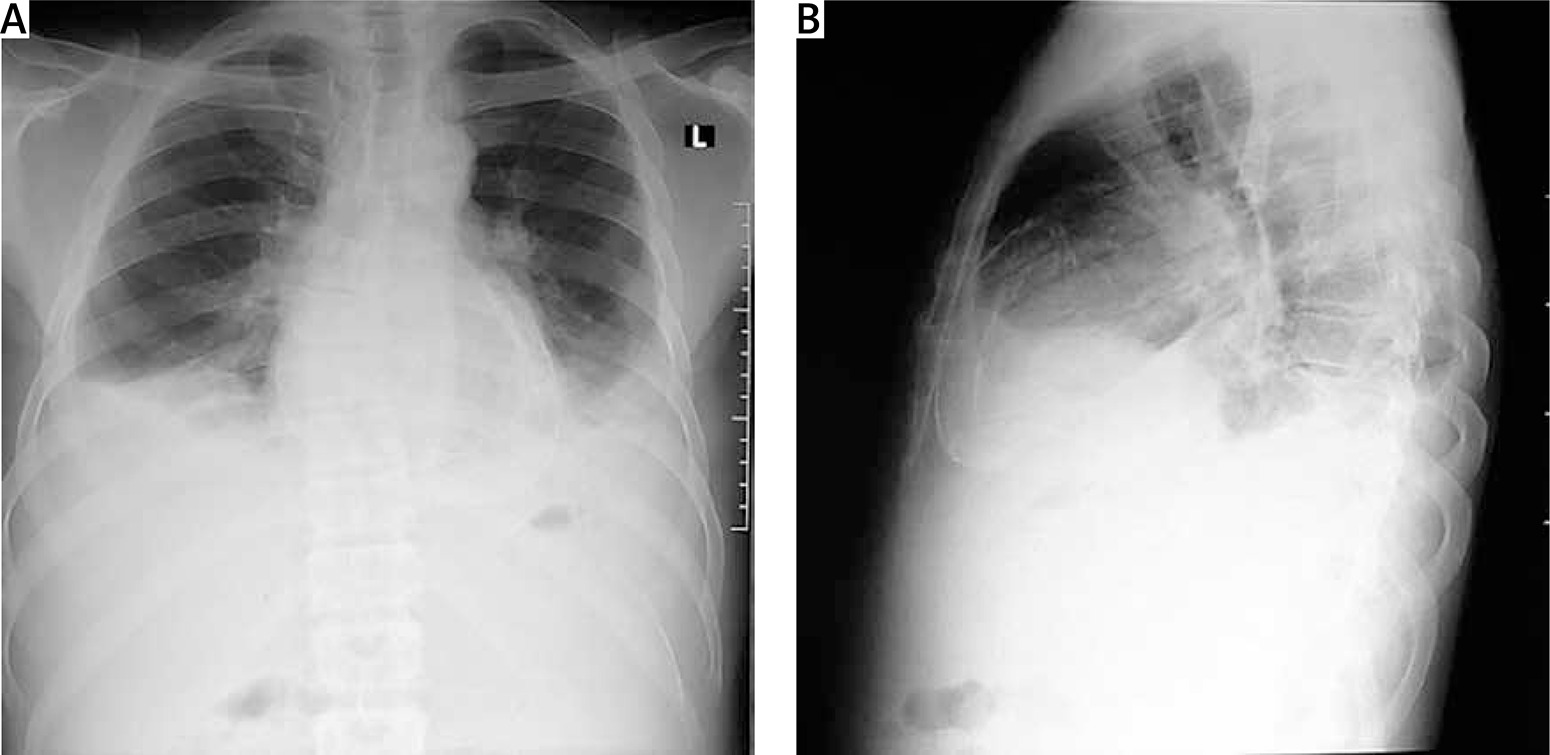

Figure 2

Chest X-ray of one of the patients with calcific constrictive pericarditis showing the pericardial calcification

Chest X-ray in patients with constrictive pericarditis may show small or normal cardiac size but presence of cardiomegaly does not rule out constriction [7]. Presence of pericardial calcification – best seen on anterior, oblique or lateral views – is highly suggestive of chronic constrictive pericarditis [1]. However, it has been reported in less than 30% of surgically confirmed cases of constrictive pericarditis [11, 13, 16]. This is consistent with our current study where 2 (20%) out of the ten cases studied showed calcification on both the chest and CT scan, as shown in Figures 2 and 3. Far superior diagnostic yields are achieved with the use of echocardiogram, cardiac CT or magnetic resonance imaging (MRI) [13]. Cardiac CT scan or MRI provides a better assessment of pericardial thickness and calcifications and visualization of any abnormal ventricular contours caused by the constriction [11, 16]. Echocardiography features indicative of constrictive physiology include respiration-related ventricular septal shift, preserved or increased medial mitral annular e-velocity and prominent hepatic vein expiratory diastolic flow reversals [17]. Currently, the use of cardiac catheterization in the diagnosis of constrictive pericarditis is decreasing due to the increased diagnostic accuracy of echocardiography, CT scanning and MRI [13]. However, cardiac catheterization is the gold standard for diagnosis in the event of indeterminate findings with the non-invasive tests [11]. The current study employed two main modalities to confirm the diagnosis of constrictive pericarditis, namely chest CT scan and echocardiography with supporting evidence from chest X-ray and ECG. Six (60%) out of the 10 patients had ECG, 9 had chest X-ray, 8 had echocardiography and 4 had chest CT scan. Three (30%) had confirmation of the diagnosis from both echocardiography and chest CT scan, as shown in Table II.